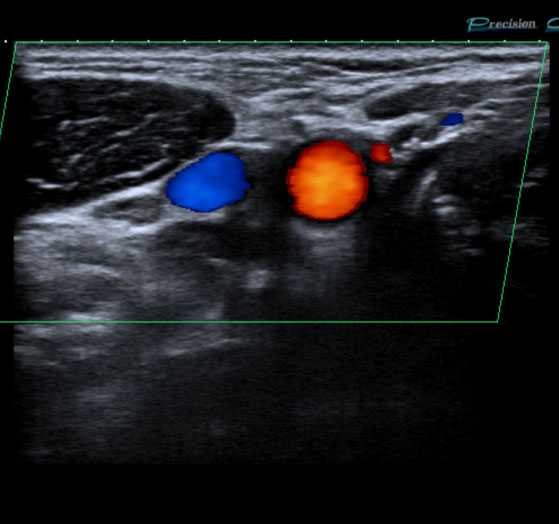

Gefäßultraschall /

Farbdopplersonographie

Die Farbdopplersonographie ist eine zuverlässige Methode zur Beurteilung von Arterien und Venen. Die Farbdopplersonographie kann einerseits Veränderungen der Gefäßwände (z.B. arteriosklerotische Plaques) und dadurch resultierende Engstellen (Stenosen) nachweisen, andererseits durch Blutflussgeschwindigkeitsmessungen den Schweregrad der Stenosen beurteilen. Risikofaktoren für Arteriosklerose und damit für Schlaganfall und Herzinfarkt sind z.B. erhöhte Blutfettwerte, hoher Blutdruck (Hypertonus), Nikotinkonsum.

• Die hirnversorgenden Arterien (speziell Halsschlagader), zur Abklärung von Durchblutungsstörungen, Schwindelattacken, Sehstörungen, Ohrensausen (Tinnitus) oder bei unklaren pulsierenden Tumoren am Hals.